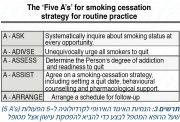

| 15:14, 10 במרץ 2016 | Smoking cessation3.jpg (קובץ) |  |

226 קילו־בייטים | Motyk | 1 | |

| 14:55, 10 במרץ 2016 | Smoking cessation2.jpg (קובץ) |  |

72 קילו־בייטים | Motyk | 1 | |

| 13:54, 10 במרץ 2016 | Smoking cessation1.jpg (קובץ) |  |

111 קילו־בייטים | Motyk | 1 | |